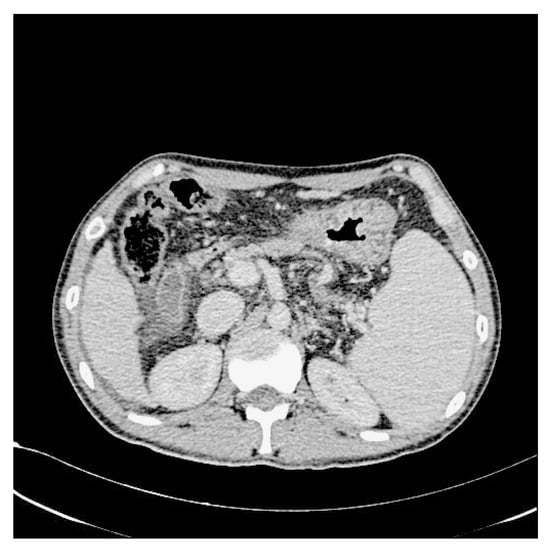

In addition, we used WGIF [38] to enhance the picture and obtain an image with stronger texture features to facilitate training after completion. Figure 3 and Figure 4 illustrate the comparison between the original and enhanced images, showcasing the augmentation of strong classification texture features. The original image, as depicted in Figure 3, demonstrates limited texture details and a relatively lower discriminative potential. However, upon applying advanced image enhancement techniques, as depicted in Figure 4, the texture features undergo substantial enrichment, resulting in heightened discriminative capabilities.

Figure 4.

After increasing the contrast.